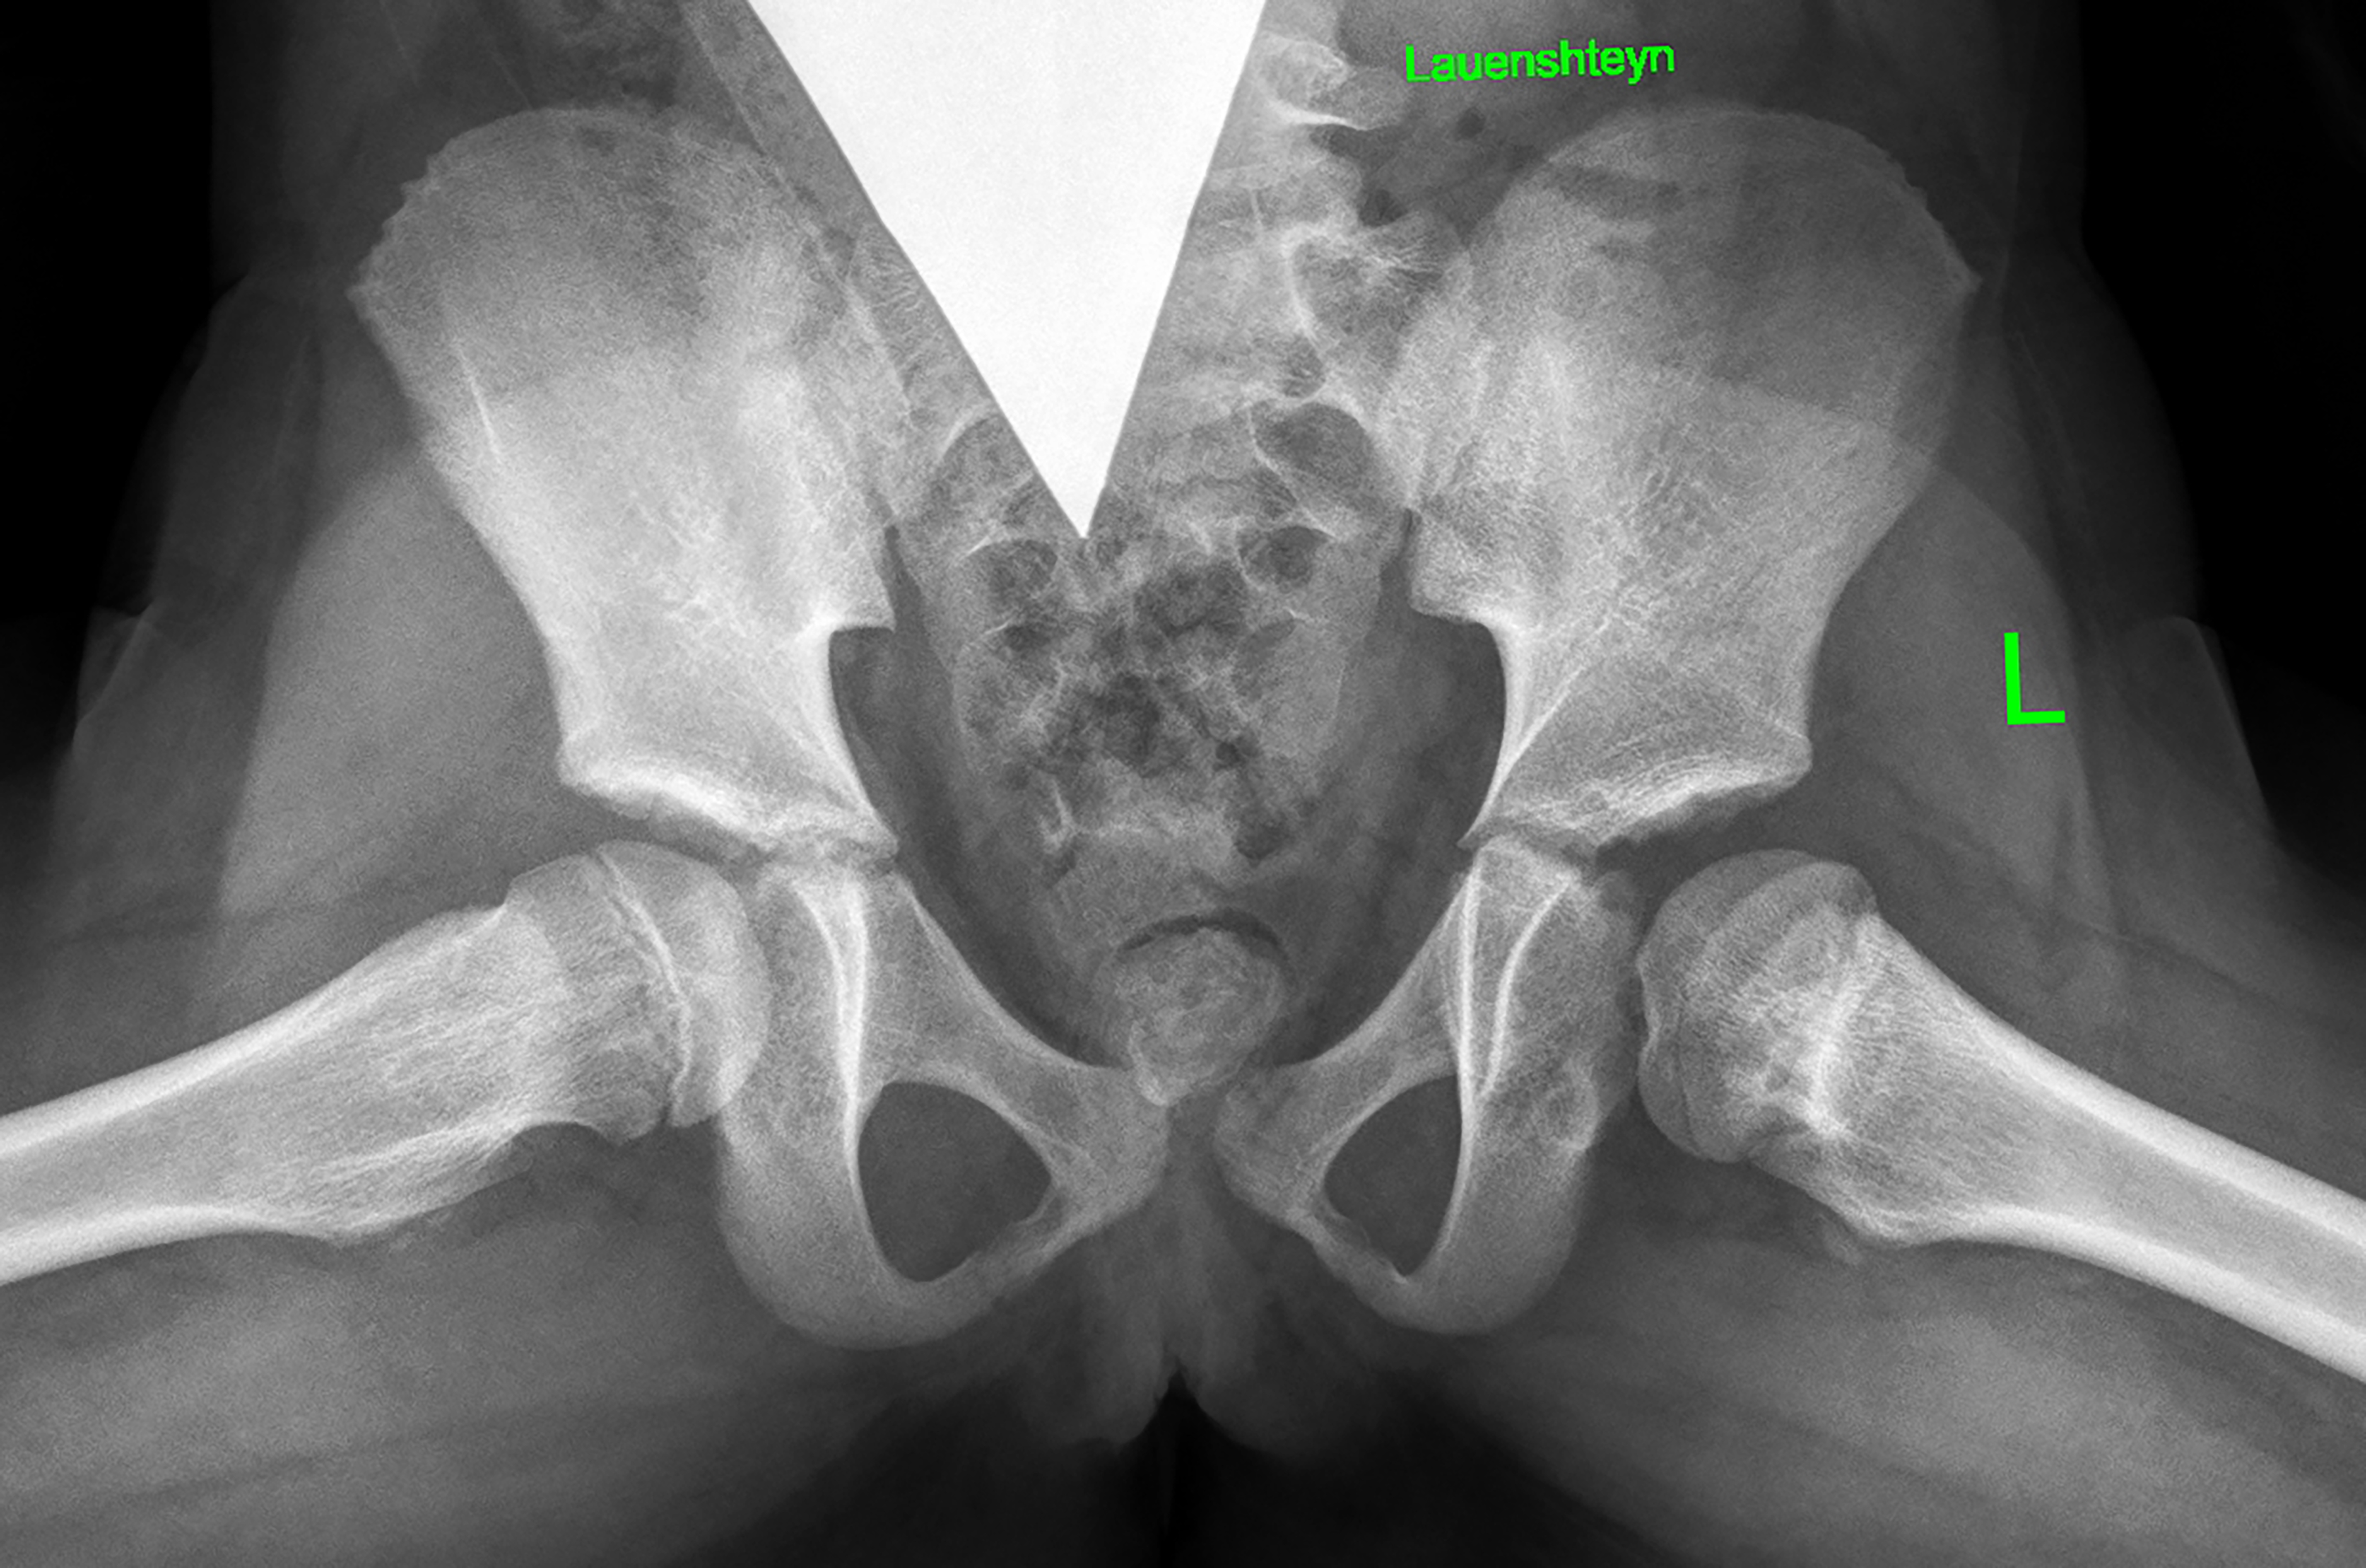

2) последствия гематогенного остеомиелита (септического артрита) — 101 (28,9 %) ребенок. В эту группу также вошли пациенты, перенесшие внутриутробные инфекции и хирургические вмешательства на первом году жизни по поводу врожденных пороков сердца, атрезии пищевода, кишечной непроходимости, трахеопищеводных свищей, осложнившиеся инфекционным поражением тазобедренных суставов (рис. 4);

Рис. 4. Рентгенограммы пациентки Ж., 7 лет. Последствия гематогенного остеомиелита — многоплоскостная деформация проксимального отдела бедренной кости с высоким положением большого вертела слева: а — прямая проекция; б — проекция по Лауэнштейну